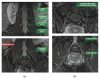

Magnetic resonance neurography is a high-resolution imaging technique that allows evaluating different neurological pathologies in correlation to clinical and the electrophysiological data. The aim of this article is to present a review on the anatomy of the lumbosacral plexus nerves, along with imaging protocols, interpretation pitfalls, and most common pathologies that should be recognized by the radiologist: traumatic, iatrogenic, entrapment, tumoral, infectious, and inflammatory conditions. An extensive series of clinical and imaging cases is presented to illustrate key-points throughout the article.